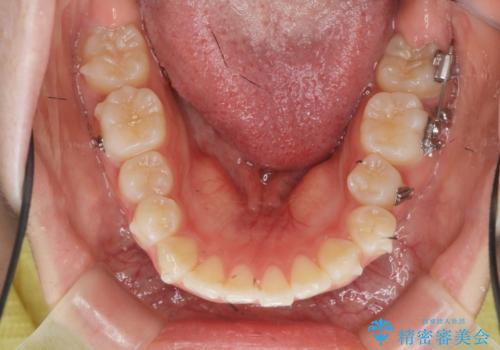

- 他院での矯正治療中に行かなくなってしまい、装置をつけたまま矯正治療の続きを希望され来院されました。

マウスピースでは並べることが難しい左下の奥歯を部分ワイヤー矯正で並べたのち、マウスピース矯正装置インビザラインで歯並びを整えていきます。